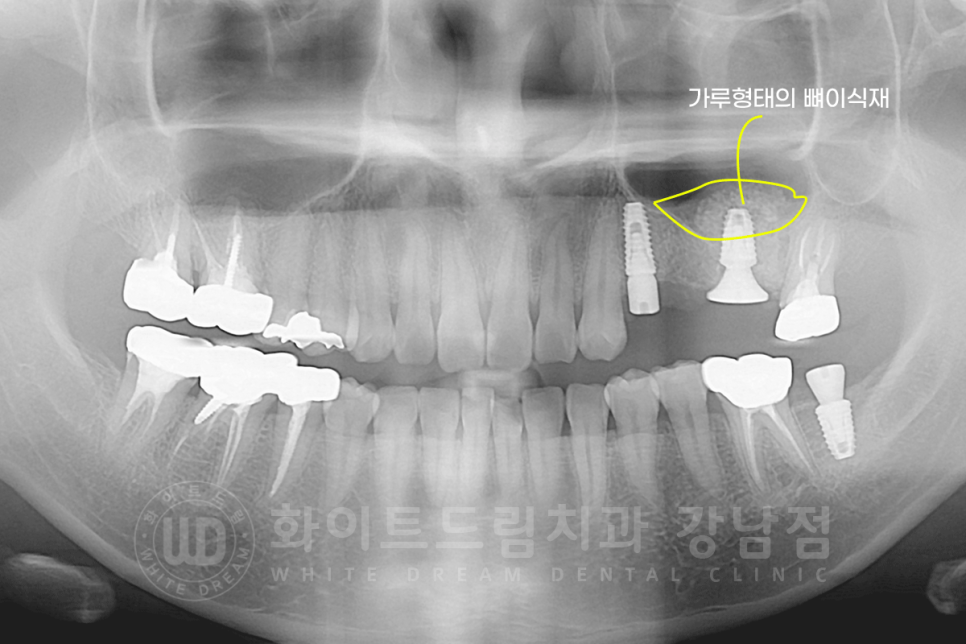

▲ lateral 술식을 이용하여 식립된 26번 임플란트입니다.

상악동 거상술 + 1차 수술 + 2차 수술을 한 번에 진행했고,

가루로 되어 있는 이식재가 주변 잇몸뼈와 잘 융합되는 회복 기간을 6개월 정도 가지기로 했습니다.

▲ 1차 + 2차 수술을 한 번에 진행하면, 구강 내 힐링 어버트먼트까지 체결됩니다.

▲ 6개월의 회복 기간 후 보철 제작에 들어갔고 최종 보철 세팅 후 x-ray입니다.

수술 전과 후의 잇몸뼈 두께를 보면 차이점이 한눈에 확인되실 겁니다. ^^

동일 인물이며, 동일 환경에서 촬영되었습니다.

치료 기간 : 16.10.25 - 17.05.19